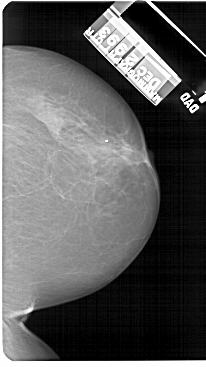

A_1565_1.RIGHT_MLO

RIGHT_MLO LINES 5071 PIXELS_PER_LINE 2896 BITS_PER_PIXEL 12 RESOLUTION 43.5 NON_OVERLAY

FILE: A_1565_1.LEFT_CC.OVERLAY

TOTAL_ABNORMALITIES 1

ABNORMALITY 1

LESION_TYPE CALCIFICATION TYPE AMORPHOUS DISTRIBUTION CLUSTERED

ASSESSMENT 4

SUBTLETY 3

PATHOLOGY BENIGN

TOTAL_OUTLINES 1

BOUNDARY